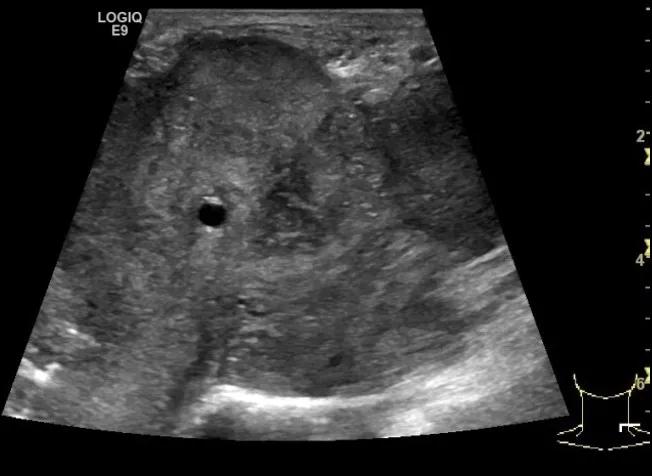

第三例是甲状腺癌患者,双侧甲状腺癌切除术后、碘治疗后一年余效果欠佳,超声显示左颈3区3枚低回声结节,穿刺示甲状腺乳头状癌转移。患者不愿意手术,希望采取局部治疗。对病灶进行液体隔离后采取热消融术,由于淋巴结较小,热消融一分钟左右完全灭活,术后增强影像显示没有脏器充填。

(病例3图例)